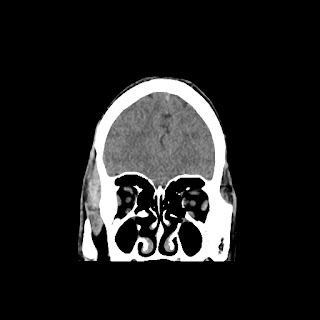

CT scan of brain images: